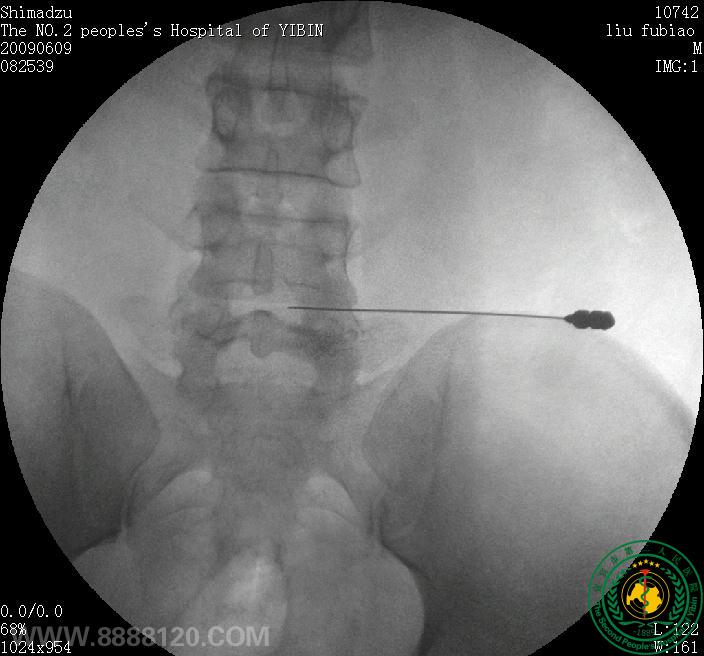

影像科介入室开展宜宾市首台腰椎间盘突出臭氧髓核消融术

影像科介入室开展宜宾市首台腰椎间盘突出臭氧髓核消融术722

宜宾市第二人民医院 图文